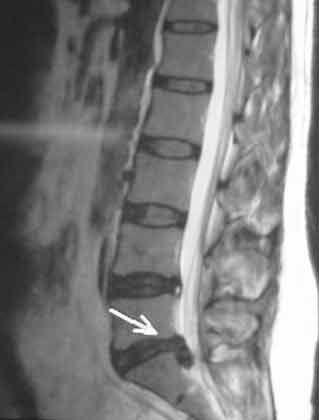

A young lady who has had previous back surgery presented to us with a new disc herniation at the same level. Her previous microdiscectomy had required an extended hospital stay because of medical complications with the patient. She had tried ample physical therapy and injections without any pain relief. She had been missing work for multiple months and was concerned she would lose her job.

She opted for the endoscopic posterolateral discectomy. Under local anesthesia [similar to dental work], the discomfort is minimized with the injected numbing medications. A small camera was placed next to the herniated disc while the patient was awake; the herniated disc was then removed. The patient felt immediate significant relief of her pain; the strength in her leg was back to normal, and she no longer felt any numbness in her legs.* She was able to go home in a few hours; about 3 months after the procedure, the patient continues to be pain free and is back to her normal activities.